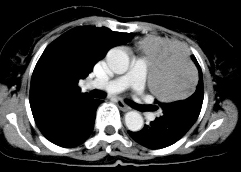

病历摘要:女,56岁。因胸部不适,2月来诊,无发热,无咯血。起病以来体重明显减轻。查体:左胸呼吸音减弱,左上胸扣诊浊音。胸部X线片示“左上肺占位病变”。做胸部CT线检查。

1.诊断是什么?

2.诊断依据是什么?

3.鉴别诊断有哪些?